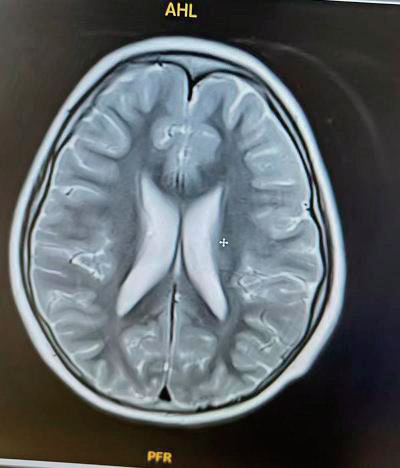

几乎所有患儿都可能出现大运动、精细运动、语言发育迟缓,伴随肌张力低下;部分患者可能表现为癫痫发作;部分患儿还会出现髓鞘形成延迟,脑室周围白质病变,脑室扩大,小脑、脑干、胼胝体发育不良等脑部结构异常。行为方面,约 1/3 患儿有孤独症谱系障碍,还可能出现焦虑、社交互动受限、注意力缺陷、低挫折耐受性等异常。另外,还可能有双侧或单侧感音神经性听力损失。

(头颅核磁双侧脑室扩大表现 图片来源:White-Sutton综合征临床表型扩展及治疗尝试:病例系列报告. 临床儿科杂志, 44(1), 38-43.)